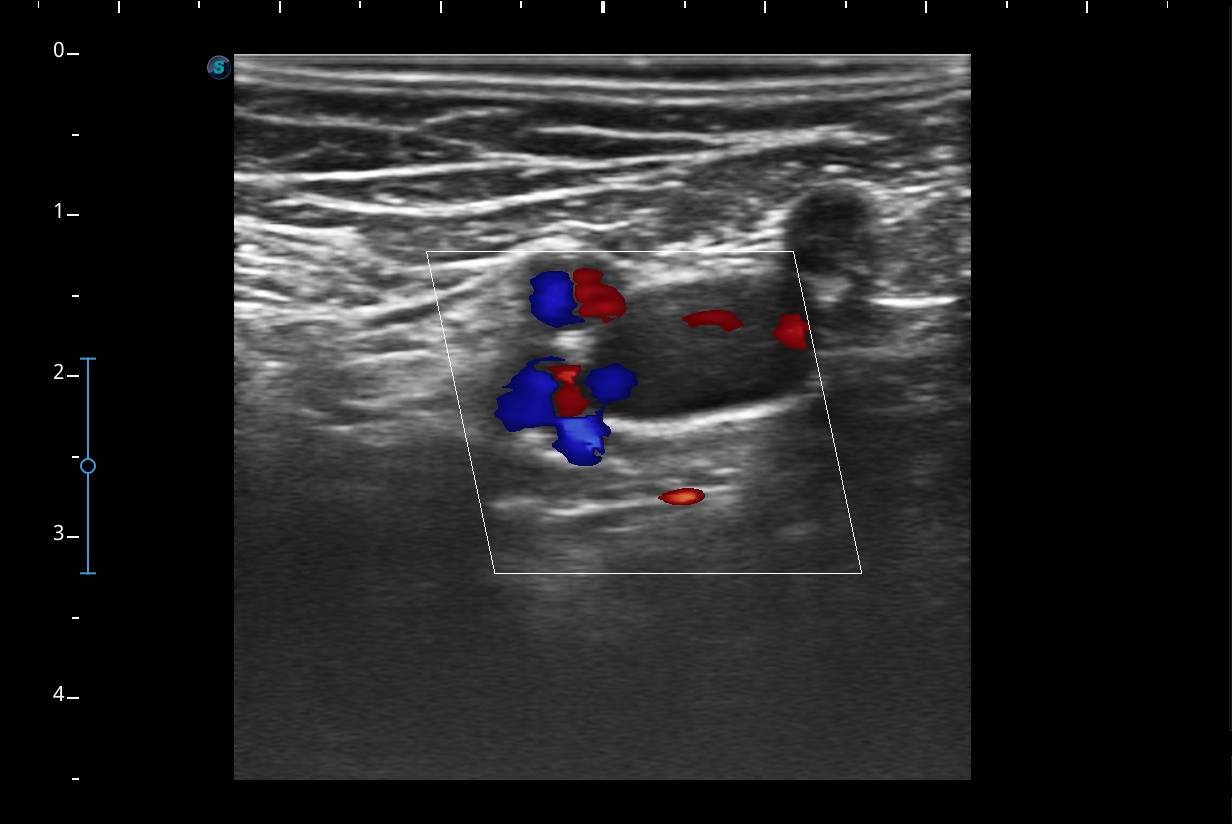

Mujer de 44 años, que presenta desde hace 2-3 semanas dolor e impotencia funcional en la pierna derecha con aumento de volumen y eritema de pantorrilla ipsilateral que en un inicio se trató como rotura fibrilar para la que se pauta reposo y tratamiento analgésico oral. Ha mejorado muy levemente pero persiste dolor en el hueco popliteo e impotencia funcional.Descripción de los hallazgos ecográficos y las imágenes más relevantes para la resolución del caso

A nivel del hueco poplíteo se visualiza presencia de trombosis de la vena poplítea, no así en localizaciones proximales.Otras pruebas complementarias realizadas (si existen)